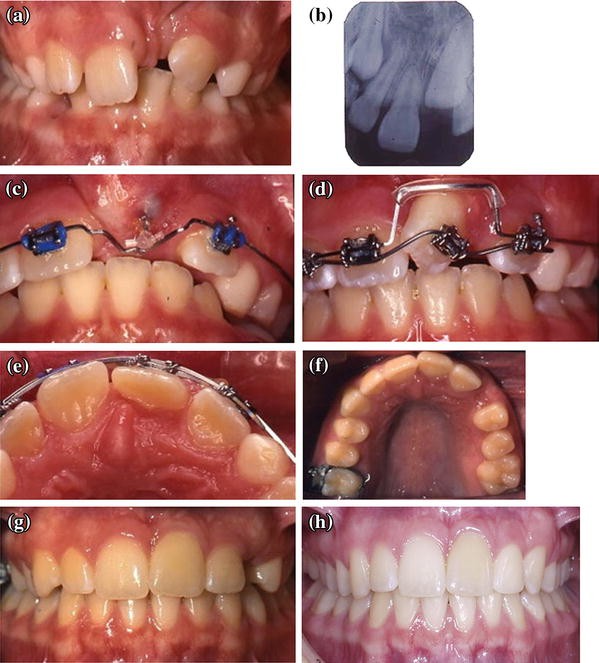

Clinical Recommendations For Management Of Mesiodens And Unerupted Permanent Maxillary Central Incisors Springerlink